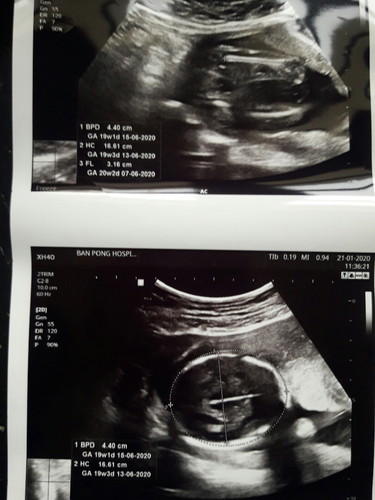

รบกวนแม่ๆช่วยดูหน่อยนะค่ะ แม่เห็นเป็นอะไรกันมั้งค่ะ ตอนซาวด์หมอก็ให้ดูว่าตรงไหนเป็นตรงไหนอยู่ พอปริ้นออกมาแทบมองไม่เห็น แล้วบอกว่ายังอ่อนมองไม่เห็นๆราบๆน่าจะ ผญ.มีใครใบซาวด์มัวๆแบบนี้ไม่ค่ะ?

น่าจะผญ.ค่ะ เห็นชัดอยู่ มุมหว่างขา แต่ยังไงรอหมอเป็นคนฟันธงนะคะ